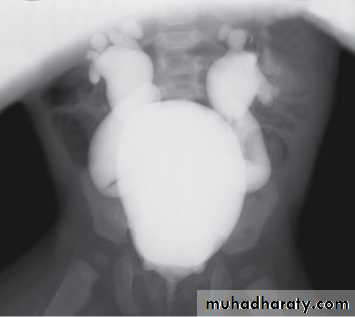

Grading of VUR

The degree of reflux is graded I–V.Grading is based on the appearance of contrast agent in the collecting system during voiding cystourethrography (VCUG(.

The VCUG:

the definitive examination

to diagnose and grade reflux and establish reversible causes

must include a voiding phase:

in some cases, reflux may be seen only during the elevated intravesical pressures associated with micturition.

in visualizing the urethra, may allow the diagnosis of outflow obstruction to be made (e.g., posterior urethral valves).

MCUG